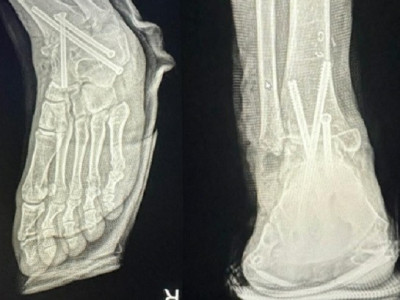

이슈 http://v.daum.net/v/20231216072610241 병원 실수로 멀쩡한 발목뼈를 절단해 철심 3개를 박은 모습. 연합뉴스 서울 …